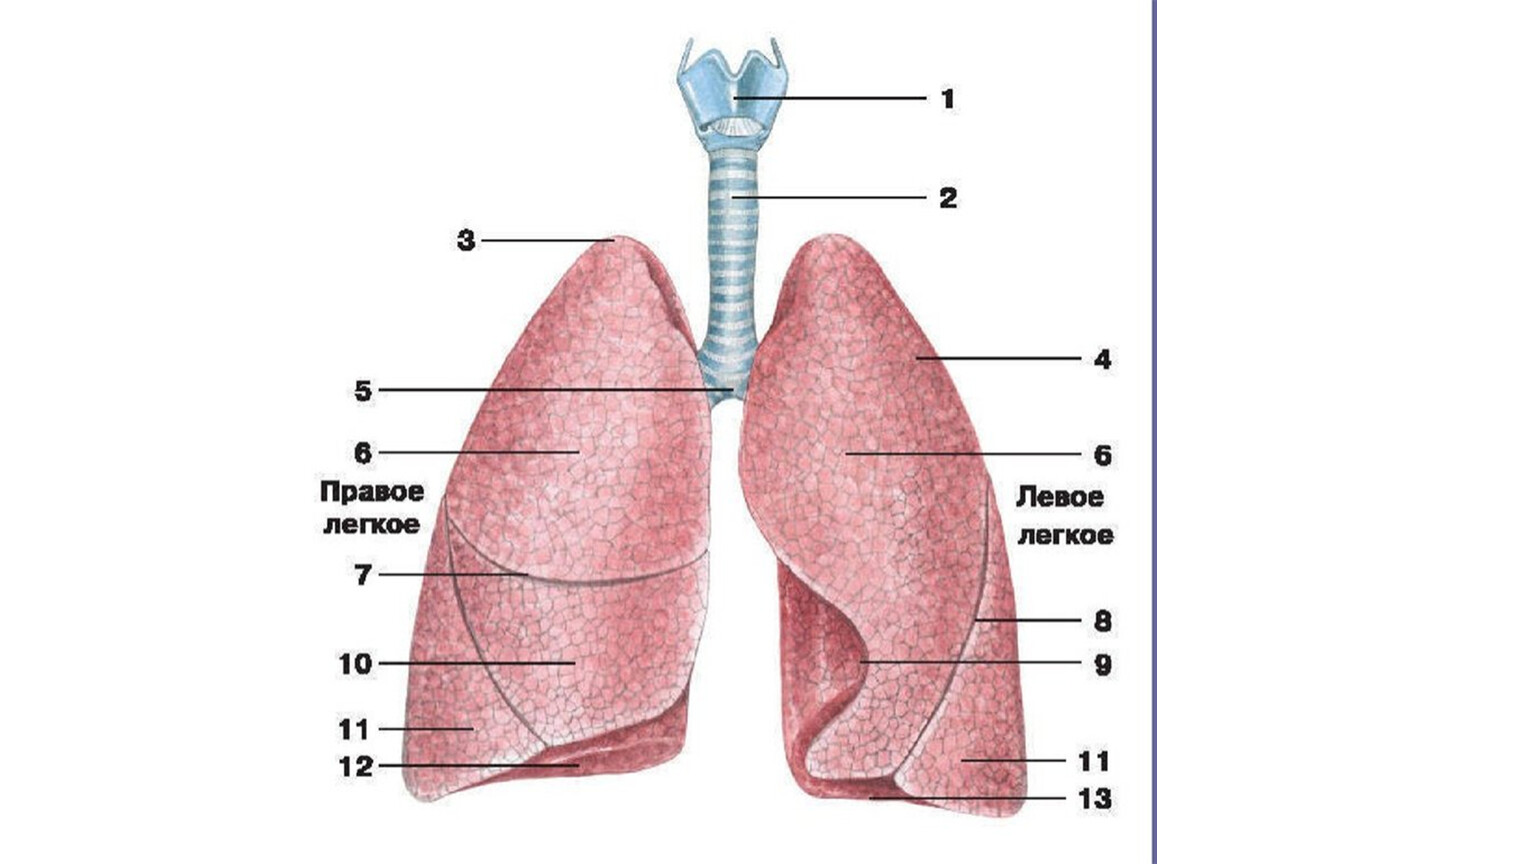

Анатомические изображения сегментов легких различных животных

Раздел: Другие животные